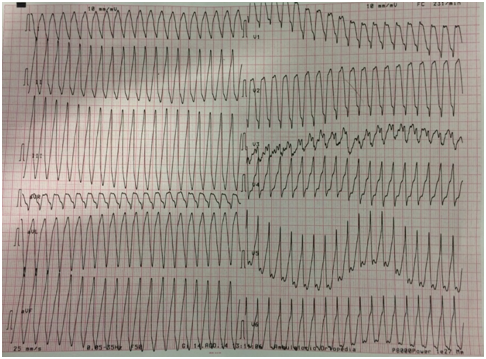

Absence of symptoms and clinical events until 14.08.2014 when he felt palpitation during strenuous physical activity (running).

ECG recorded at Sessa Aurunca Hospital showed monomorphic ventricular tachycardia

Successful Electrical Cardioversion with 200 J DC Shock

Ecg After Electrical Cardioversion